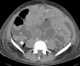

Desmoplastic small round cell tumor

Desmoplastic small-round-cell tumor (DSRCT) is an aggressive and rare cancer that primarily occurs as masses in the abdomen. Other areas affected may include the lymph nodes, the lining of the abdomen, diaphragm, spleen, liver, chest wall, skull, spinal cord, large intestine, small intestine, bladder, brain, lungs, testicles, ovaries, and the pelvis. [Source: Wikipedia ]